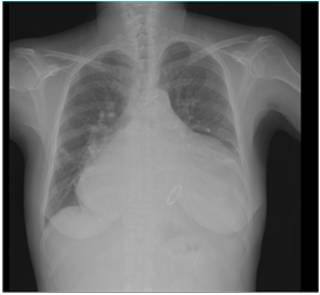

胸片提示:双肺纹理增强模糊,左侧少量胸腔积液,心胸比0.81。